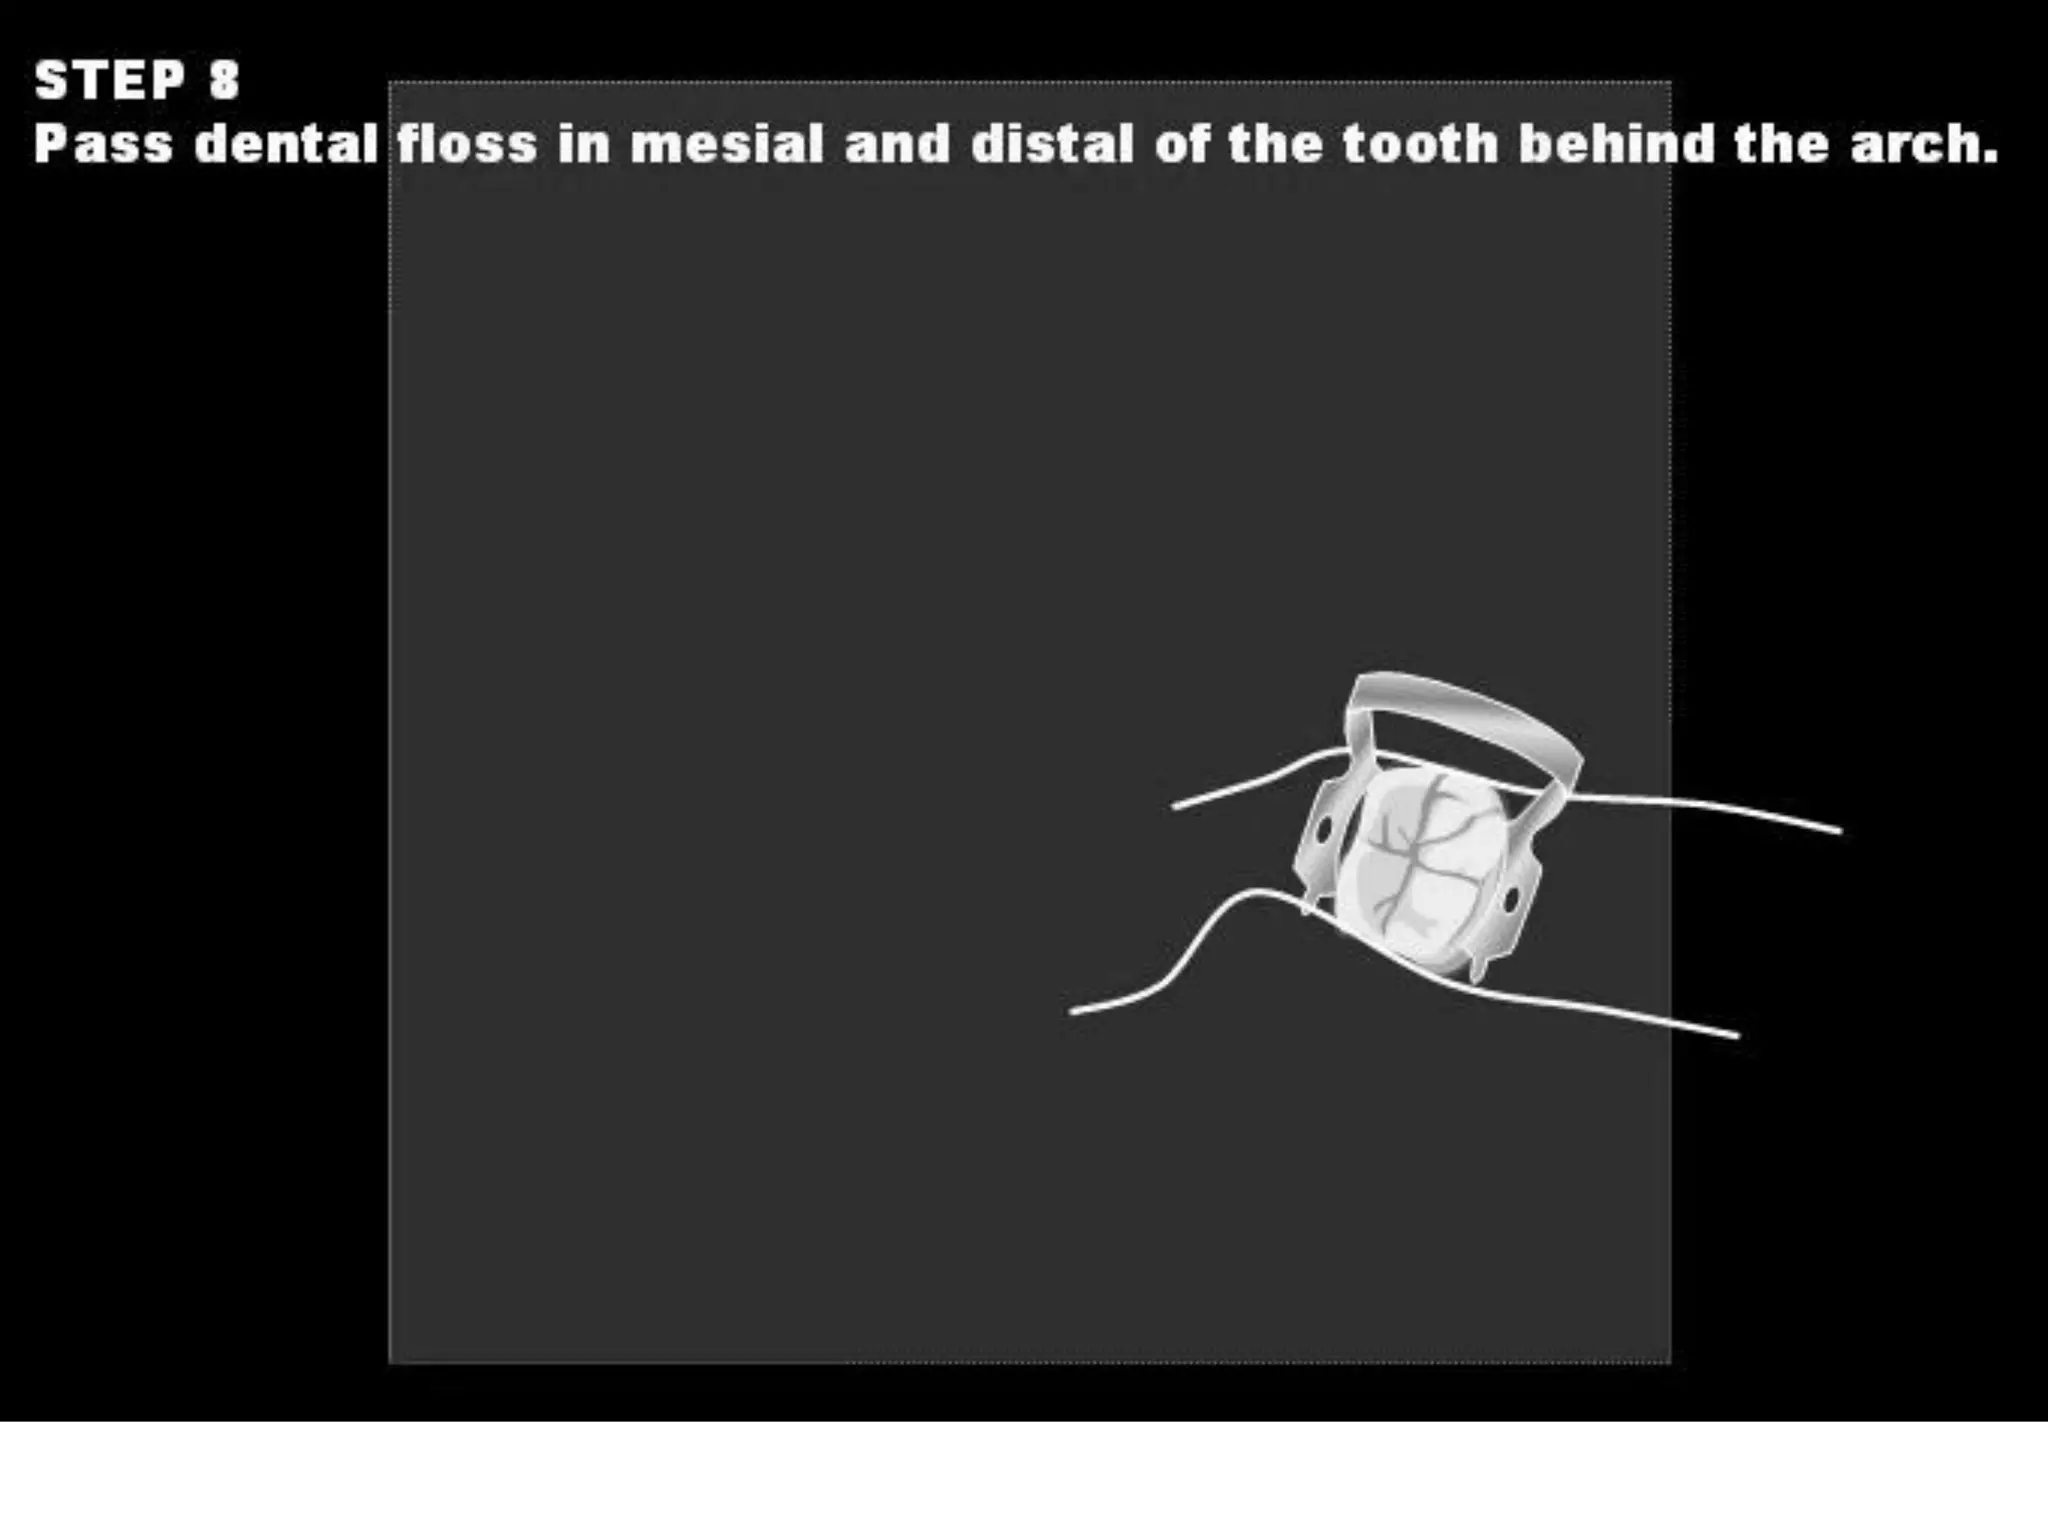

This document discusses the materials and components used for rubber dam isolation in dentistry. It describes the different types of rubber dam materials including color options and napkins to absorb moisture. It also outlines the tools needed such as punches to make holes, templates and stamps to guide hole placement, clamps to secure the dam, and other accessories like wedges and lubricant. Finally, it provides guidance on punching holes for different types of teeth and properly placing clamps in the rubber dam.